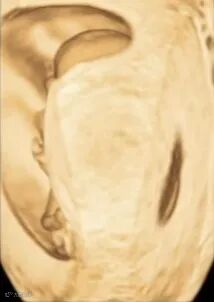

接着我们还可以进一步处理容积数据,获得我们想要观察的其他平面,这里以鼻后三角为例。

选择双幅画面,a平面为胎儿正中矢状切面,观察点设置在胎儿鼻骨位置,旋转a平面,可以在b平面获取胎儿面部冠状切面,显示鼻后三角平面。